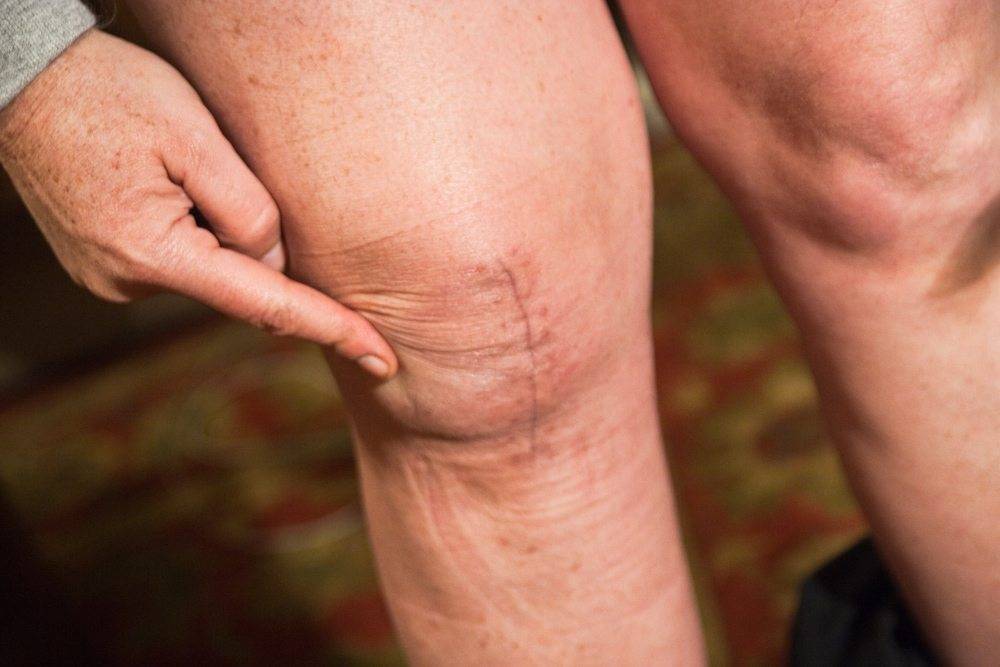

Шов через два месяца после миниинвазвной операции.

А так выглядит шов после классической операции. Он неровный, потому что у пациента — проблема с сосудами, и их прошлось обходить во время разреза.